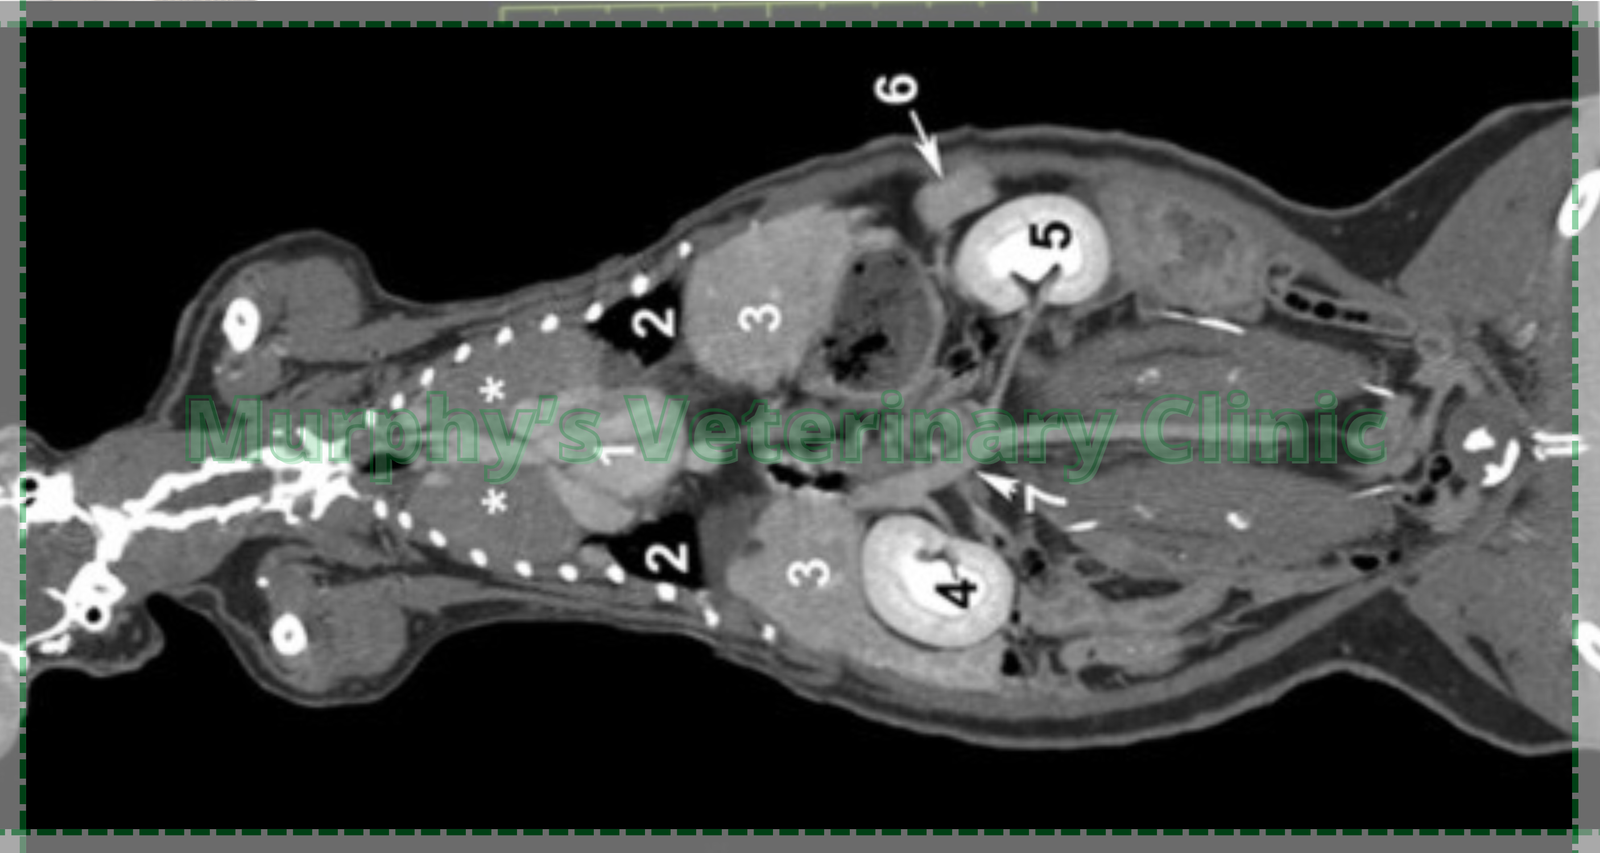

| CT-Scan | Tumor and internal injury detection | High clarity, 3D visualization |

These methods help ensure accurate early disease detection in pets with tailored diagnostic insights.